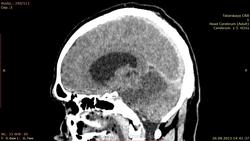

мужчина 1976 г. р. прислали вот такое исследование с направлением "онмк" точка ((( как расценить изменения мозжечка? аномалия?

Какая аномалия? Инфаркт обширный в бассейне основной артерии. Поражены мозжечок со стволом + затылочные доли. Последние поражены в меньшей степени, вследствие компенсации кровотока через ЗСА. Внутренняя тривентрикулярная гидроцефалия. V4 правой позвоночной артерии и основная артерия имеют повышенную плотность, что может соответствовать тромбозу (не всегда). При таких инфарктах обычно бывает окклюзионная гидроцефалия, требующая дренирования желудочковой системы. Тут, по всей видимости, состоянее тяжелое.

Редкостная картина в плане локализации, да еще и с нарастанием отека-опасно.

Какое-то странное симметричное поражение в бассейнах кровоснабжения обеих верхних мозжечковых артерий. Почему нет изменений в бассейнах нижних мозжечковых артерий? Как это объяснить?

Так объясняется анатомией. Отхождение передних и задних нижних мозжечковых артерий (AICA, PICA) проксимальнее уровня поражения и наоборот - поражение выше уровня отхождения описанных артерий.

Получается, что тромбирование (окклюзия) базиллярной артерии произошло дистальнее отхождения передних нижних мозжечковых артерий. Спасибо за презентацию.